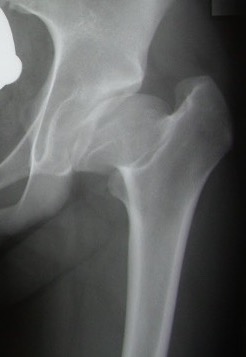

2. Resorption / fragmentation

Duration : 6/12

Pathologic Process

- necrotic bone irregularly resorbed / creeping substitution

- replaced with vascular fibrous tissue

- may be associated with collapse

XRay - Fragmentation of Physis